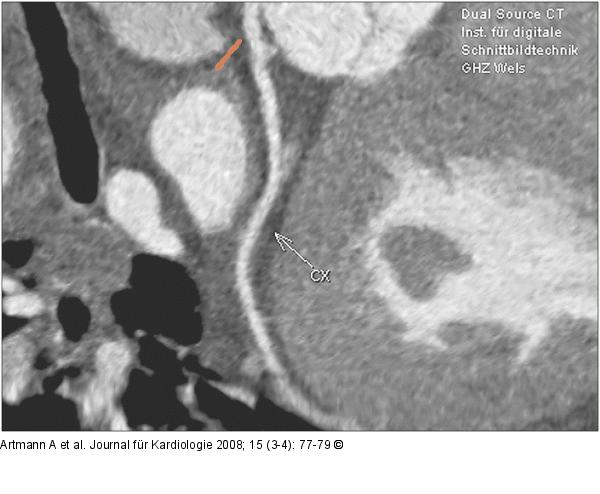

Abbildung 6: CX - MPR CX (circumflex artery), MPR- (Multiplanare Reformation) Darstellung |

Abbildung 6: CX - MPR

CX (circumflex artery), MPR- (Multiplanare Reformation) Darstellung |